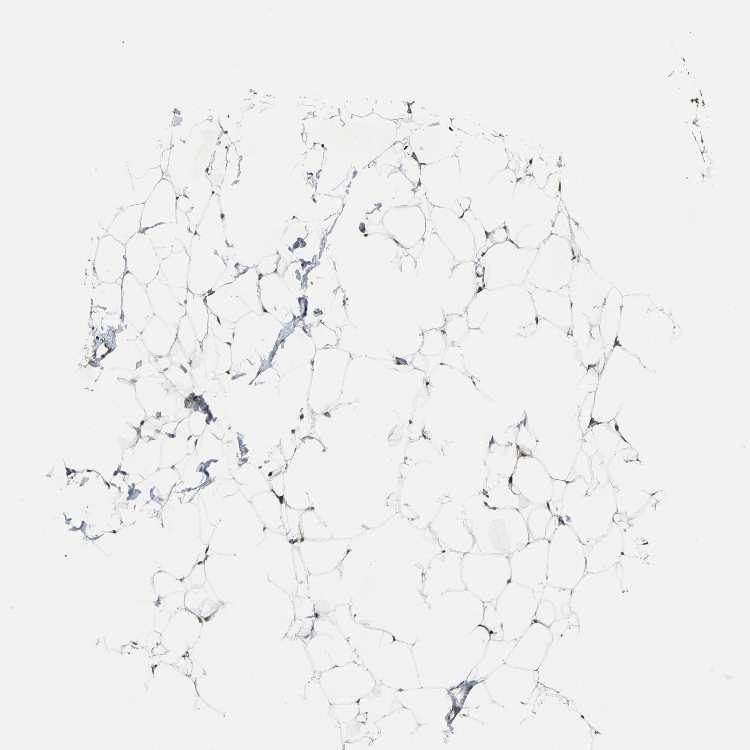

SOFT TISSUE 2 - Antibody stainingi

Antibody staining in the annotated cell types in the current human tissue is reported as not detected, low, medium, or high, based on conventional immunohistochemistry profiling in selected tissues. This score is based on the combination of the staining intensity and fraction of stained cells.

Each image is clickable and will lead to virtual microscopy that enables deeper exploration of all samples and also displays staining intensity scores, fraction scores and subcellular localization as well as patient and tissue information for each sample.

Antibody HPA006616

Fibroblasts Medium

Peripheral nerve Low